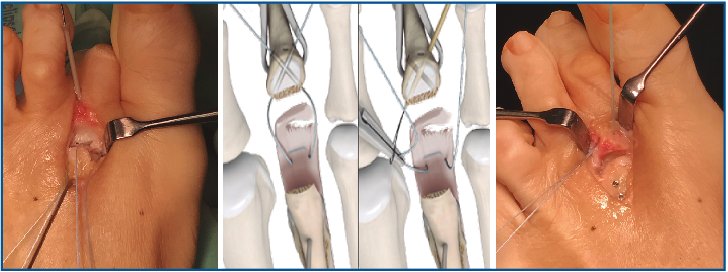

7. Fijamos la osteotomía de Weil con el acortamiento metatarsal deseado y previamente establecido (se recomienda un acortamiento mínimo de 2-3 mm) (Figura 12). Con la articulación MTF perfectamente reducida y el dedo en 30° de flexión plantar, tensamos las suturas recuperadas en el dorso de F1, hasta llevar firmemente la placa plantar a su base, y anudamos (Figura 13).

Figura 13. Tensado y anudado individual de las suturas en el dorso de F1, confirmando la reducción estable de la articulación metatarsofalángica.

8. Confirmamos la reducción de la articulación MTF simulando la carga. Habitualmente asociamos alargamiento de tendones extensores y reparación de la garra o deformidades a nivel IFP o interfalángica distal (IFD).

Corregimos las posibles desviaciones en el plano horizontal mediante plicatura capsular medial o lateral. En casos de desviaciones severas se puede asociar una transferencia del extensor corto como plastia del ligamento colateral defectuoso, tunelizándolo a través de la base de F1 y cuello MT (Figura 14).